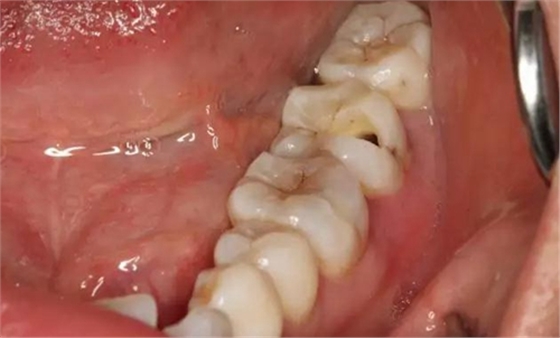

圖3. 取出棉球口內(nèi)發(fā)現(xiàn)37合面有開髓孔,探針出血,頰側(cè)牙齦紅腫。